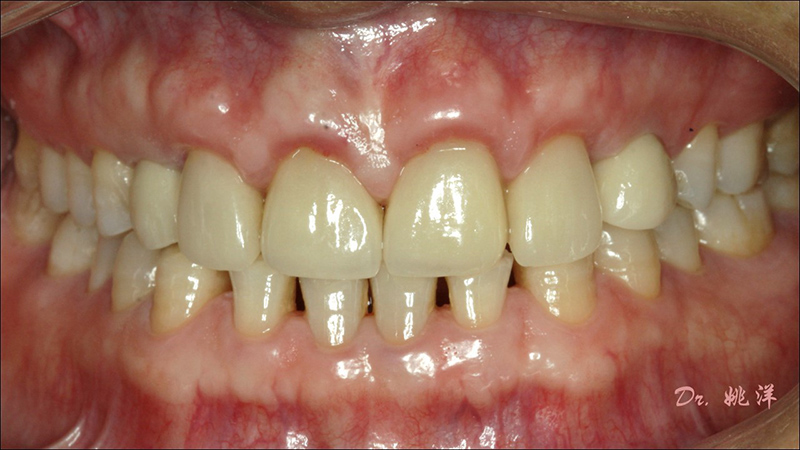

從最終修復(fù)效果可以看出:23,24間隙不足修復(fù)兩顆,修復(fù)為1顆牙。因為經(jīng)過數(shù)字化設(shè)計和精確導(dǎo)航植入,修復(fù)體齦緣協(xié)調(diào)自然

術(shù)后照片

恢復(fù)了正常的淺覆合淺覆蓋